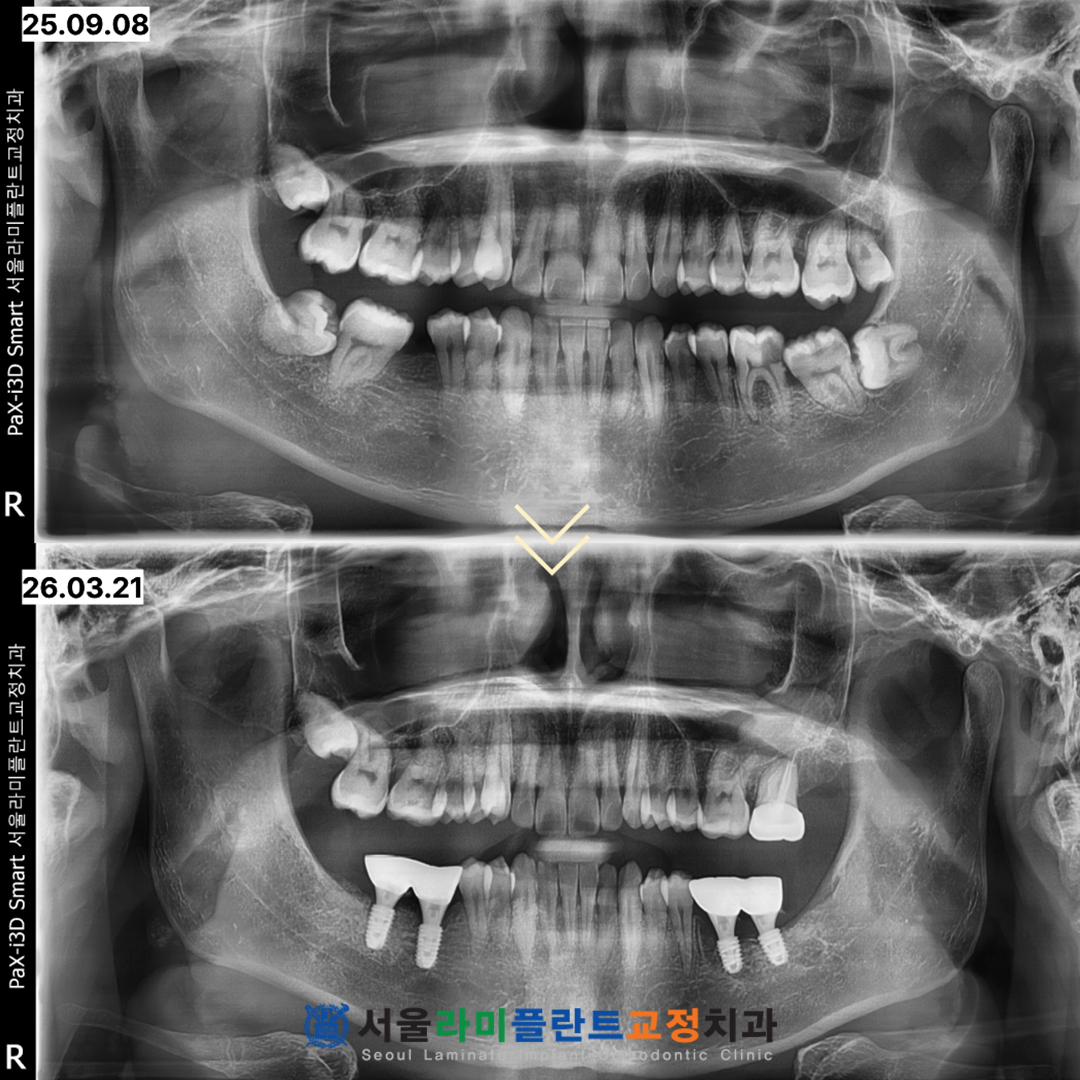

2025년 9월 8일부터 시작되어

2026년 3월 21일에

모든 과정이 종료되었습니다.

이 기간 동안 총 6개의 치아를 발치하고

4개의 임플란트를 성공적으로 식립하였으며

1개 치아의 신경치료와

크라운 수복까지 마쳤습니다.